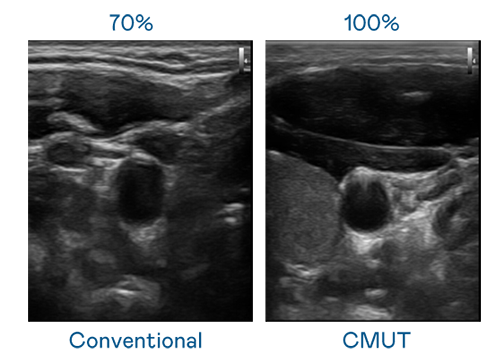

CMUT 技術是一種用電容式微機電元件來產生超音波訊號的技術。與傳統 PZT 壓電式技術相比,CMUT 頻寬增加 30%,更寬頻的超音波訊號讓影像解析度大幅提升,是實現高影像品質醫療超音波掃描、促進精準醫療發展的關鍵技術。

超音波影像的解析度高低,首先取決於探頭能發出的訊號頻寬。利来 CMUT 可提供高清晰的超音波訊號,提供高頻寬、高靈敏度、影像紋理細節更高的超音波影像,協助醫護人員縮短影像判讀時間及利用精準的醫療影像進行診斷。